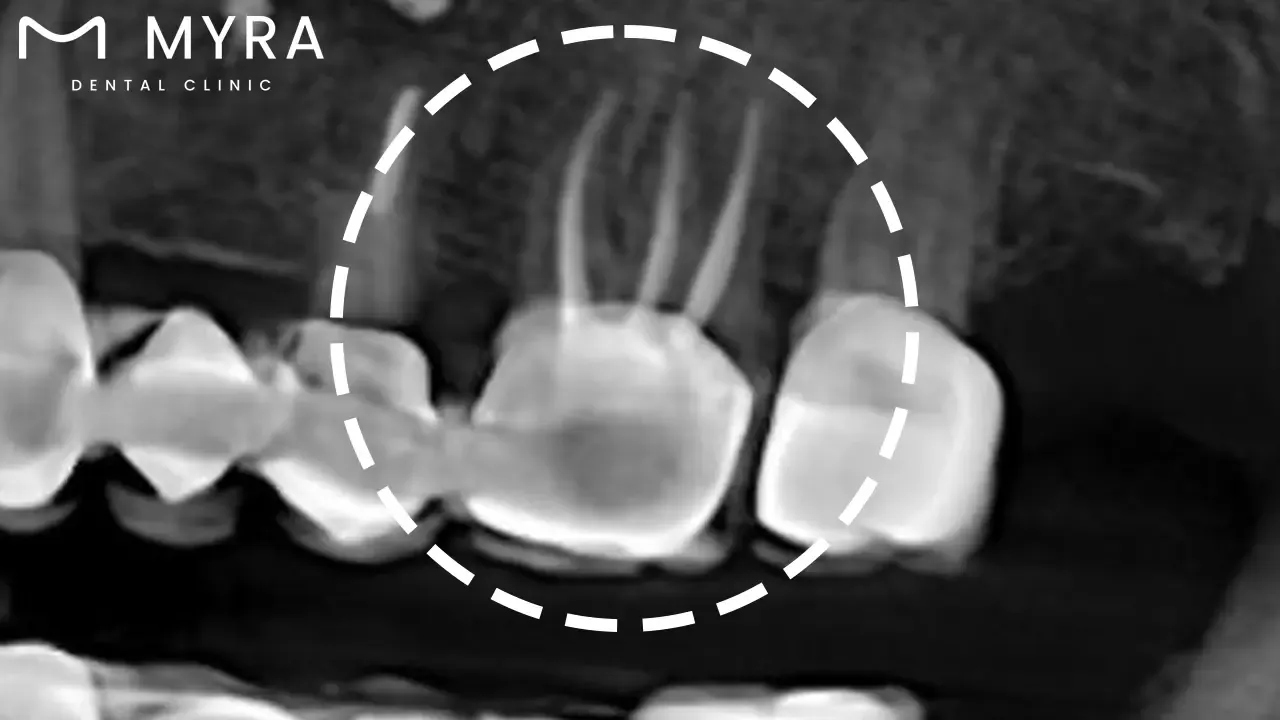

Examination with X-rays is a crucial initial step in the procedure for dental root canal treatments. It takes radiographic images of the patient's teeth and jaws to gain a comprehensive view of the affected tooth and the surrounding bone structure. X-rays allow the dentist to clearly see the interior aspects of the teeth and gums that aren’t visible to the naked eye.

The importance of the procedure lies in the valuable information it provides. X-rays reveal the shape and size of the root canals and the extent of the decay or infection. It allows the dentist to identify any signs of an abscess, bone loss, or other abnormalities in the surrounding bone structures. X-rays offer a roadmap to the dentist, guiding them in their treatment plan.

The necessity of an examination with X-rays for the next steps in the procedure is vital. Data obtained from the X-rays determines how the dentist approaches the root canal treatment. Knowing the number of roots and the shape of the canals helps the dentist accurately remove all the infected tissue from the tooth. It highlights any additional canals that aren’t present or any unusual anatomy that requires a different treatment approach.

X-rays are taken during the procedure to help ensure that the cleaning and shaping of the canals are done effectively and that the filling material adequately seals the entirety of the canal. Post-procedure X-rays are necessary to assess the success of the treatment and monitor healing during follow-up visits. Examination with X-rays is an essential part of the root canal procedure, from initial diagnosis and planning to execution and follow-up. The likelihood of a successful root canal treatment greatly drops without X-rays.